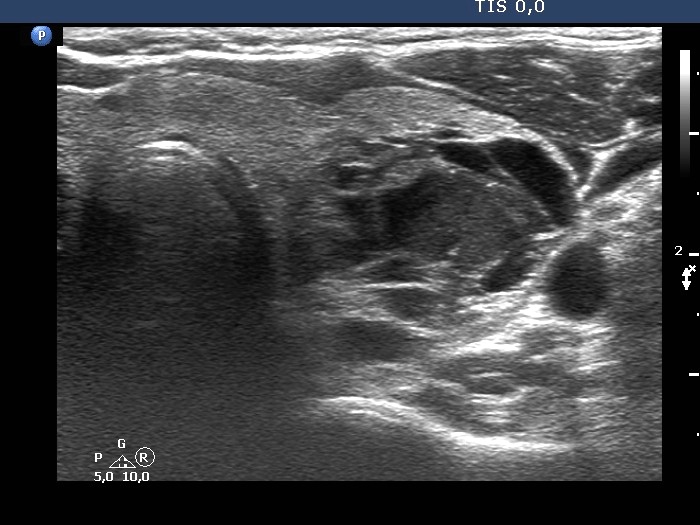

The composition of the nodule - case 142

Examination 3 years later (ultrasonographic picture 8)

Right lobe, longitudinal scan